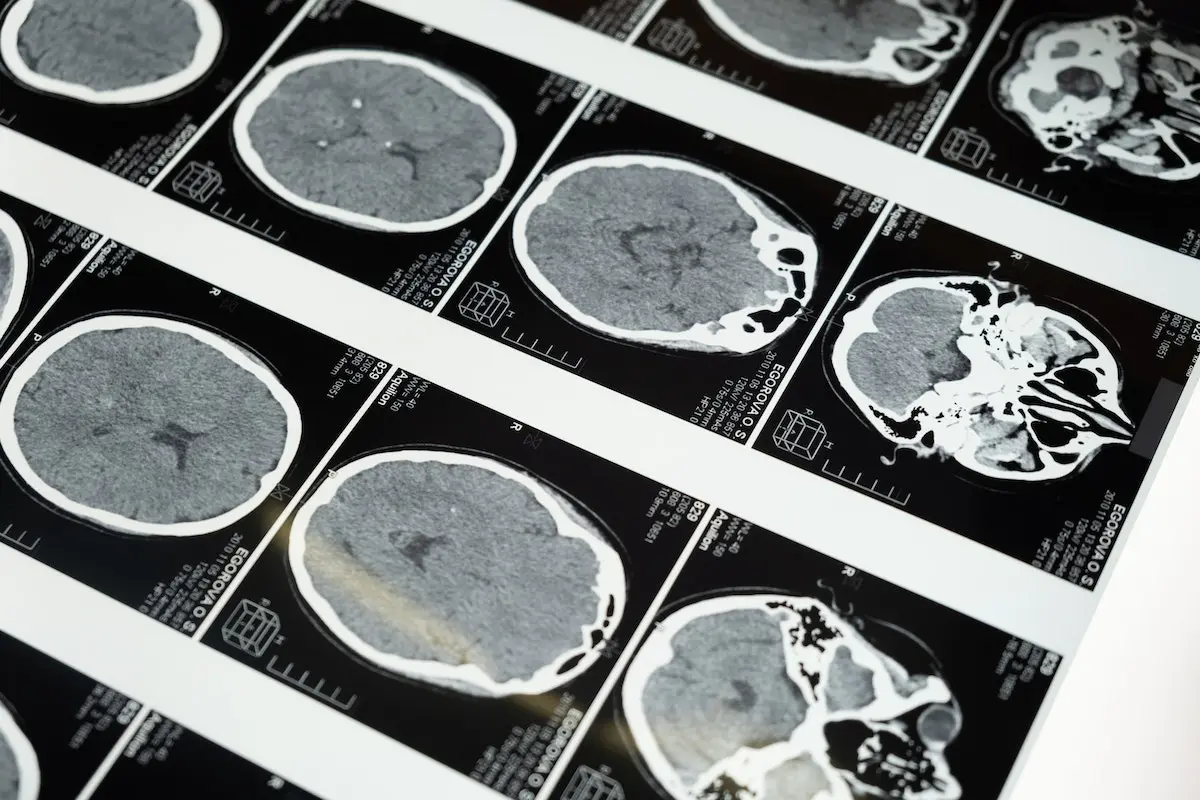

A recent study delved into the effects of mold toxins on individuals, specifically focusing on attention deficit disorder (ADD) and slowing of reaction time triggered by mold exposure. The study identified 15 subjects who exhibited these symptoms due to exposure to mold toxins. To objectively measure these impairments, researchers employed the Test of Variables of Attention (TOVA), a comprehensive tool providing quantifiable data on attention span and reaction time.

The results were striking: mold-exposed subjects demonstrated significant decreases in attention span and notable increases in reaction time compared to controls. However, after undergoing ten sessions of hyperbaric oxygen treatment (HBOT), a statistically significant improvement was observed in both these areas. This initial study suggests that HBOT could be a viable solution for individuals struggling with toxic mold exposure, offering hope for cognitive recovery and improved attention-related functions.

The intriguing aspect of HBOT lies in its multifaceted impact on the body. When individuals are exposed to mold toxins, various neurophysiological abnormalities can occur, affecting brain functions. HBOT, in its essence, significantly increases oxygen concentration in all body tissues, even in areas with limited or blocked blood flow. This boost in oxygen supply triggers the growth of new blood vessels, enhancing circulation in regions with compromised blood flow.